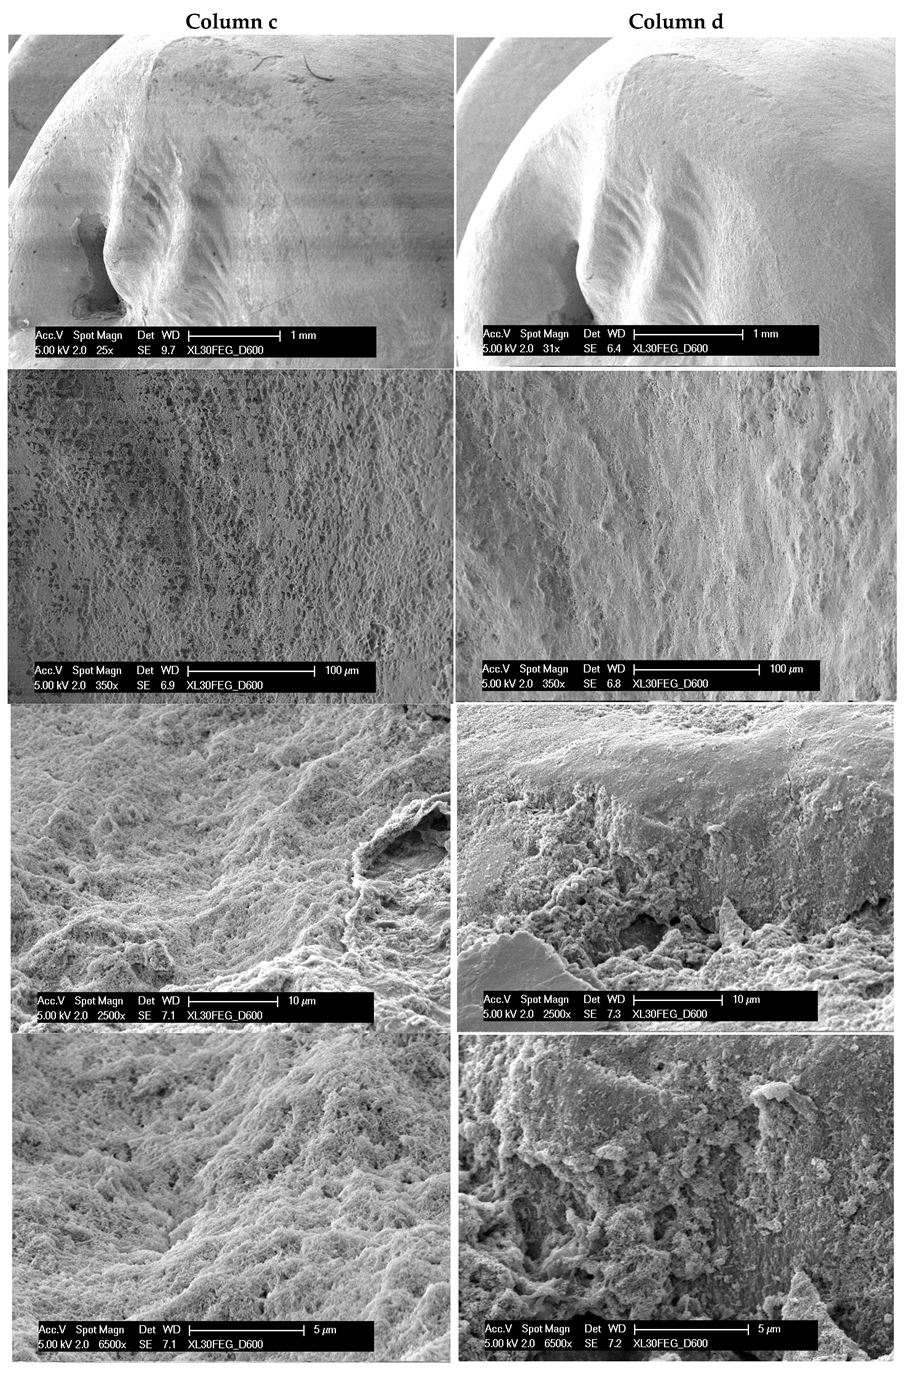

3. Results